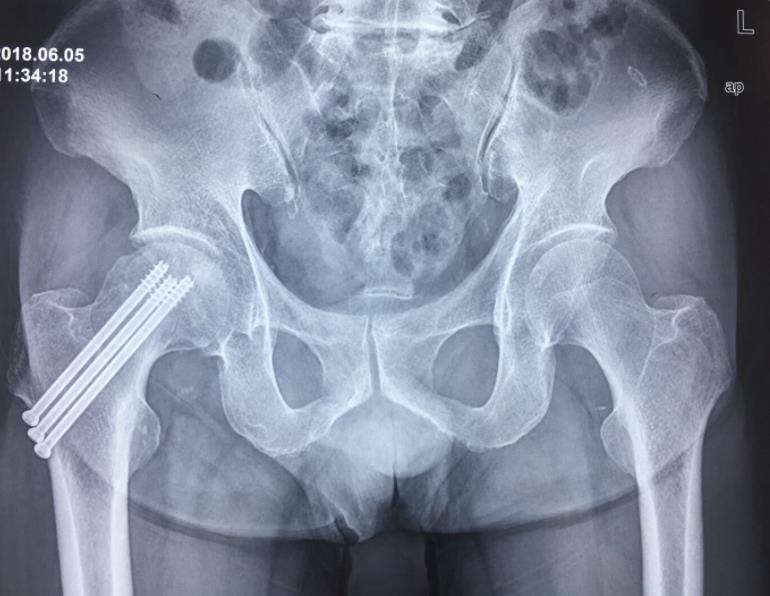

闭合复位经皮固定手术步骤

1、经皮沿股骨颈轴线置入空心钉导针,确保导针平行;

2、标准放置螺钉为倒三角形,其中下方螺钉在股骨矩,后方螺钉在后方骨皮质、研究发现倒三角形平行三枚螺钉能提供最佳的固定强度;

3、螺钉位于股骨颈四周,特别是后侧及下方,避免低于小转子方向进针,可能导致术后转子下骨折;

4、两个平面透视导针位置良好后切开皮肤,空心钻铭孔,导针引导下拧入空心钉,空心钉确保所有螺纹位于骨折线近端,螺钉头应距离软骨下骨5mm。

空心钉固定的三原则:“贴边、平行、倒品”

1、贴边是指3枚螺钉在股骨颈内,尽量靠近外围皮质。这样3枚螺钉作为一个整体,对整个骨折面可形成面状加压,如果3枚螺钉不够离散,更趋于点状加压,稳定性较差,不能较好地对抗扭转和剪切。

有研究显示,在侧位片上,螺钉的前后分布越分散,骨折不愈合发生率越低。J Bone Joint Surg Br. 2005 May: 87(5): 632-4.

图1 3枚螺钉在股骨颈内的理想位置

2、倒品有更明显的生物力学优势,CORR曾发表美国学者的一项生物力学研究,对比两种固定方式出现再骨折的负荷大小,发现倒三角再骨折的平均负荷11330N,而正三角仅7795N,差异明显,也就是说倒三角形固定可使再骨折的负荷提升45%。

图2 倒品字固定

3、平行生物力学更稳定。